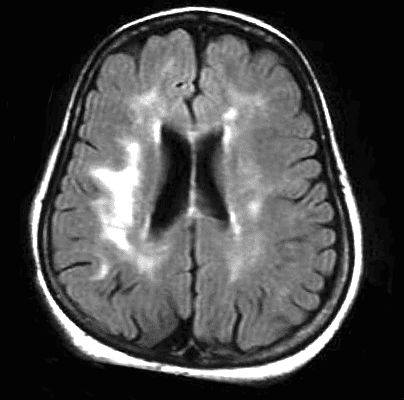

The progression of leukoaraiosis tends to follow a general pattern. Initially, periventricular lesions towards the limit (caps) of the lateral ventricles (Fig. 1) are observed spreading around them, in relation to the severity of the phenomenon, (Fig. 2).

As we have mentioned, Leukoaraiosis refers to alterations that can be detected through Computerized Axial Tomography (CAT) and brain Magnetic Nuclear Resonance (MRI) images which consist of areas of hypodensity or hyperintensity, respectively.

Of these two, the most widely used technique for the assessment of Leukoaraiosis is the brain Nuclear Magnetic Resonance imaging including T2-weighted and FLAIR sequences.